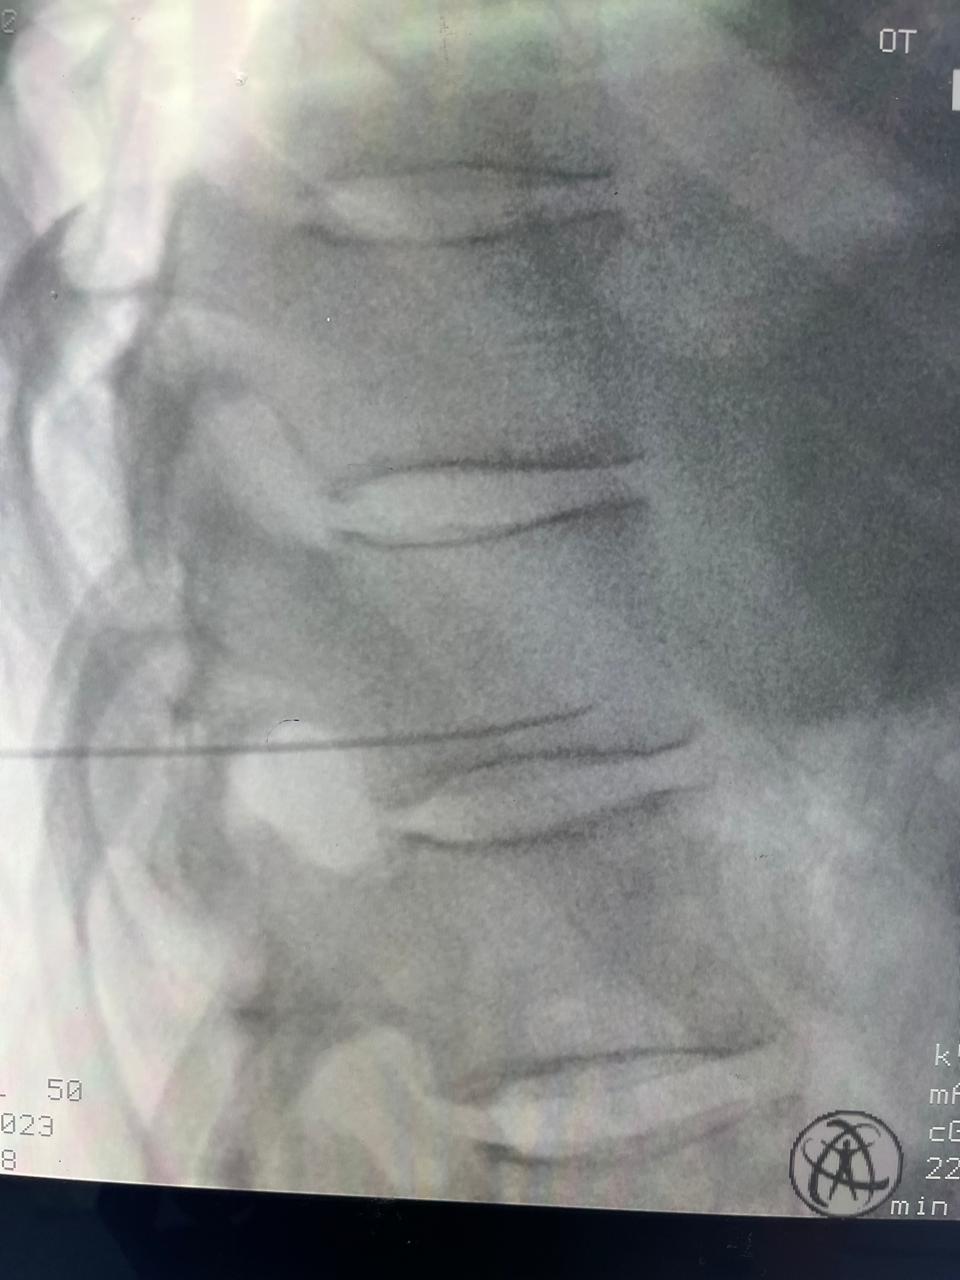

At RK Pain Management Clinic, we are dedicated to providing comprehensive, compassionate care to individuals suffering from chronic pain.